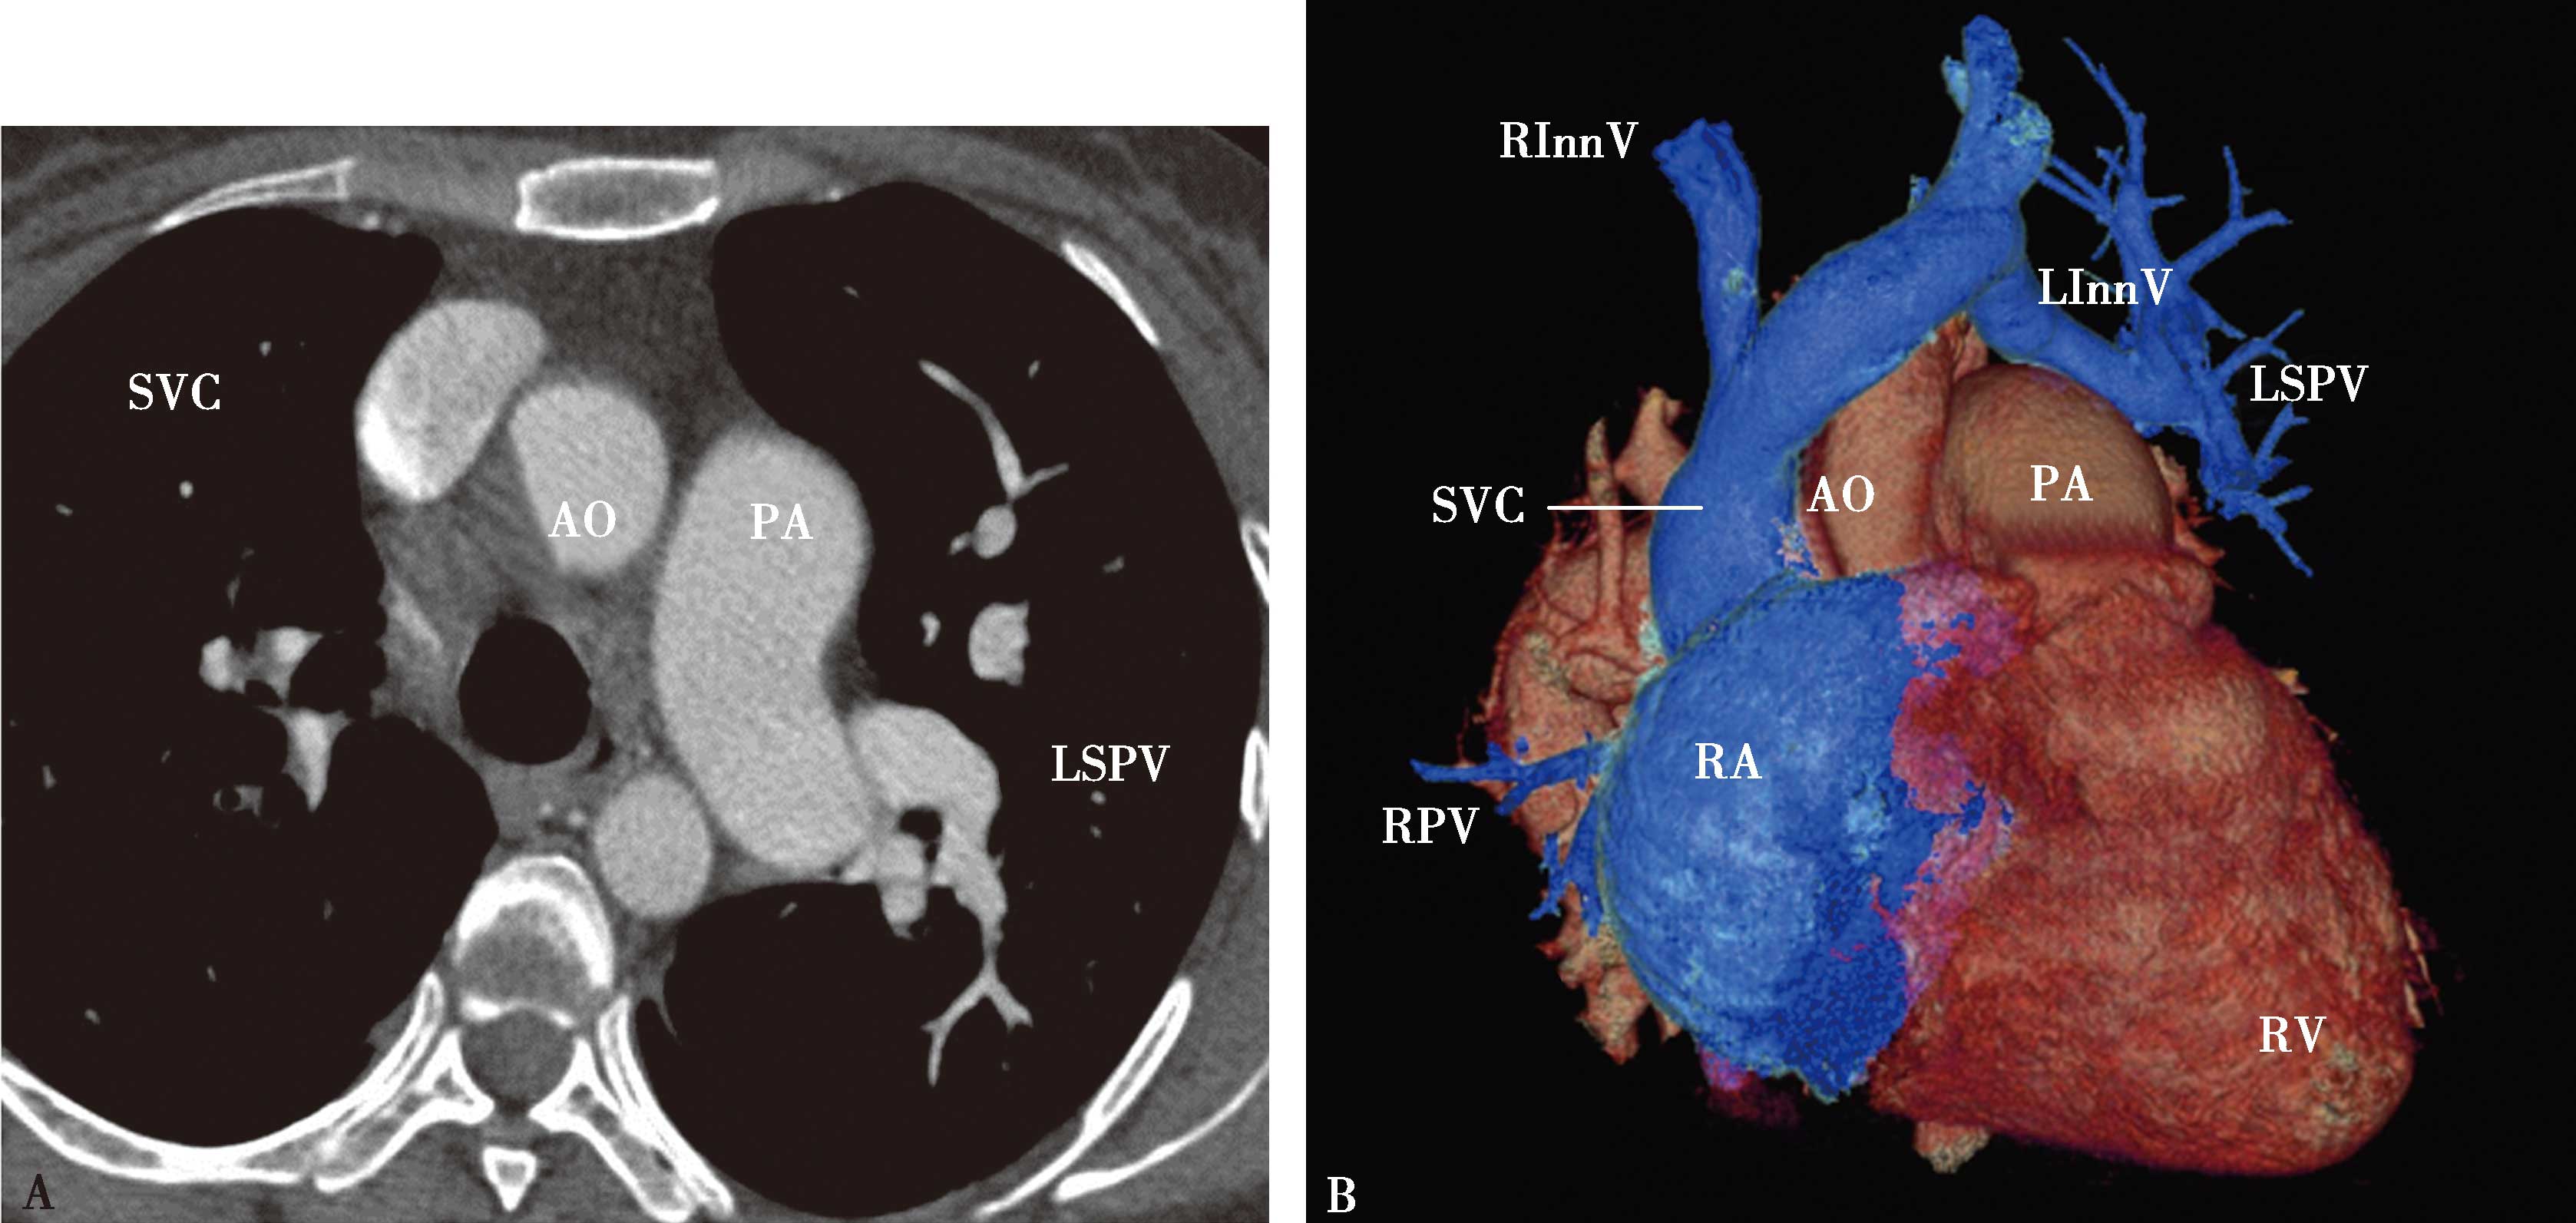

五、多排螺旋CT肺静脉造影方法

多排螺旋CT肺静脉造影检查多用于:①左心房-肺静脉检查,用以检查左心房,左心耳和肺静脉的解剖,评价肺静脉,评估左心房大小,检出左心房(耳部)血栓,指导临床诊断及射频消融治疗;②肺静脉疾患:肺静脉瘤,肺静脉狭窄,闭塞;回流异常等(包括先天性或获得性)。CT检查可以减少对有创检查的依赖、减少患者负担,有重大的优势。

5.一期扫描 当ROI的CT值达到阈值时启动增强扫描程序。第一期扫描得到完整的肺静脉-左心房图像。如果达到诊断目的,可结束扫描(图8-1-11)。

图8-1-11 肺静脉CTA检查

A.上肺静脉(↑);B.下肺静脉(↑);C.肺静脉最大密度投影。LSPV:左上肺静脉;LIPV:左下肺静脉;RSPV:右上肺静脉;RIPV:右下肺静脉